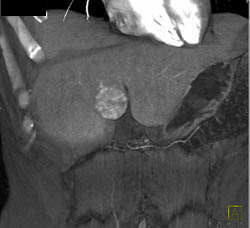

Hepatic Adenoma